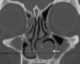

Turbinate enlargement